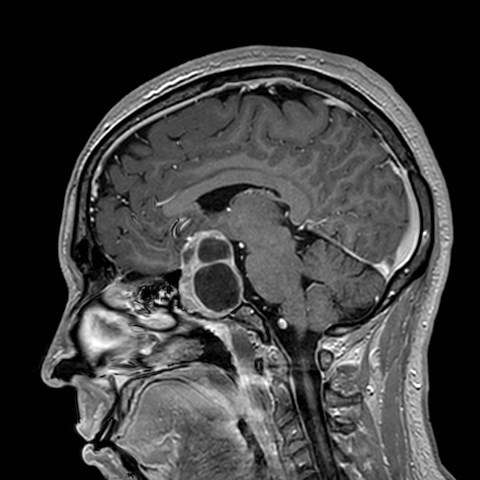

Imagenología

La resonancia magnética de hipófisis con contraste dinámico y en equipos de alta resolución (3 teslas) constituye la técnica de imagen de elección tanto para el diagnóstico inicial como para el seguimiento de los adenomas hipofisarios. Este tipo de resonancia permite una caracterización detallada del tamaño, extensión y relación del tumor con estructuras adyacentes, así como una evaluación precisa de posibles cambios en el tiempo.

En el caso de los microadenomas hipofisarios no funcionales menores de 0.5 centímetros, no se considera necesario un seguimiento por imagen, dado su escaso potencial de crecimiento o complicaciones. Sin embargo, cuando estos adenomas alcanzan o superan los 0.5 centímetros, se recomienda repetir la resonancia magnética a los seis meses, luego de forma anual durante tres años. Si no se observa crecimiento, el seguimiento puede hacerse con menor frecuencia.